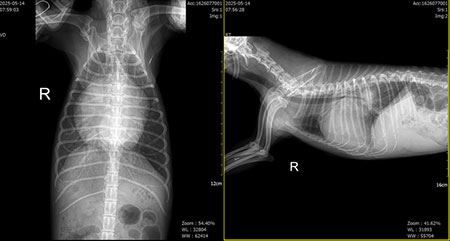

아마 이 아이에게는 모든 순간이 넘어야 하는 높은 산이었을 것이다. 멀리서 내가 할 수 있는 것은 응원 뿐. 그리고 다음날 환자의 방사선 사진이 메시지로 도착했다[그림 2, 3].

투석 만세다. 아이는 잠시 위기에서 탈출했다. 투석을 하면 신장도 위기에서 구해낼 수 있지만 폐수종도 초여과를 통해 해결할 수 있다. 이런 상황을 만들면 단 며칠 이뇨제 요구량도 감소한다.